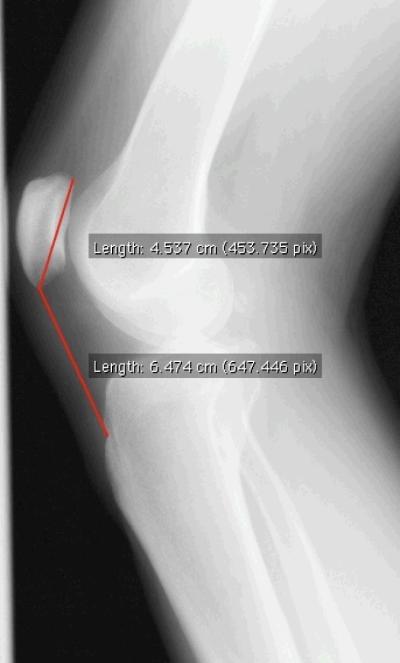

Patella alta assessment (Figure 1)

Patella alta was measured by the Insall-Salvati Ratio, calculated by dividing the length of the patellar tendon by the length of the patella measured from the lateral radiograph [8].

Patella alta was measured on the lateral semi-flexed weight bearing radiograph by the Insall-Salvati ratio (ISR). The ISR is a ratio between the length of the patellar tendon and superior-inferior length of the patella. An ISR ≥1.2 is considered patella alta [8]. The radiograph protocol was standardized across all patients and the two study sites [14] and yielded knee flexion angles of 20–50 degrees (median 39 degrees). The ISR was calculated by dividing the distance from the tibial tuberosity to the inferior pole of the patella by the length of the patella measured by the distance from the apex of the patella to its most posterior superior point. All measurements were made using Osirix digital software (Version 3.2.2). Measurement of patella alta was repeated by a primary reader (JS) and a second reader (AZ) in 10% of all knees to determine inter and intra-rater reliability. Inter and intra-rater intraclass correlation coefficients for the ISR were ≥0.9.